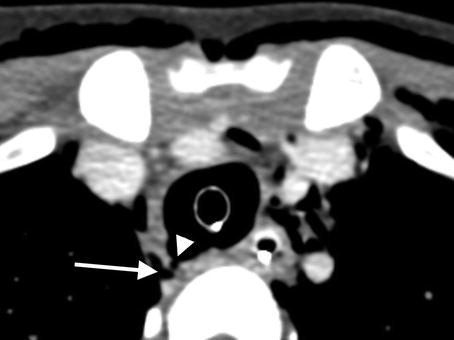

Axial image from the same CT angiogram demonstrates focal contour abnormality within the dorso-lateral quadrant of the upper trachea (arrowhead) with immediately adjacent paratracheal gas (arrow) representing the site of iatrogenic tracheal disruption. Surgical repair of the injured trachea was required